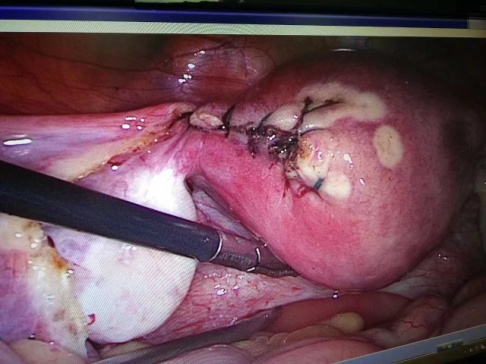

2023年9月19日下午,林芝市人民医院妇产科住院部收治了一位停经1+月、阴道流血5天、伴腹痛的孕龄女性患者,B超检查提示左侧宫角可见一直径约2.5cm包块,考虑左侧宫角妊娠,妊娠包块距浆膜层后约1.3mm,内可见胚芽及胎心搏动,妊娠指标HCG:28752 u/mL,检查提示患者为特殊的宫外孕,破裂可能性大,宫角妊娠破裂短时间可出现大出血导致休克,甚至危及生命等可能,汪医生查看患者情况后告知,该患者需要急诊行手术治疗,指示管床医生完善检查并做好术前准备,紧急送手术室行腹腔镜探查。在汪医生的指导下,本次手术由我院妇产科主任姚冬花医生主刀独立完成。手术中姚主任凭借个人扎实的腔镜基础,顺利完成手术,术后1天患者下床自由活动,术后3天患者痊愈出院。首例由本院医生主刀的腹腔镜下宫角妊娠手术圆满成功,标志着妇产科腹腔镜诊疗技术再上新台阶。

姚冬花主任主刀独立完成腹腔镜下宫角妊娠手术

术前

术后